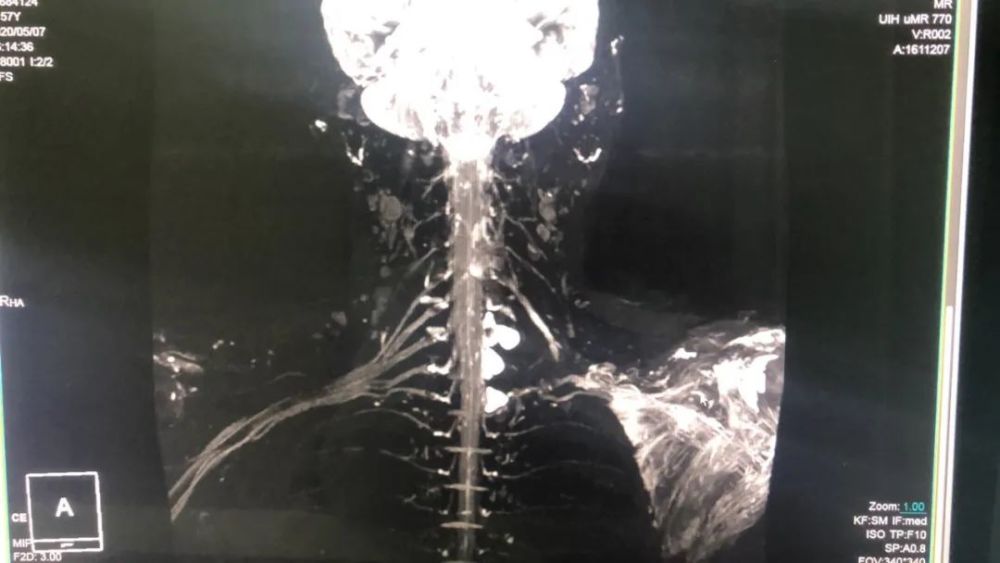

臂丛神经-mip

其它 3t磁共振临床应用及新业务简介(神经成像篇) 写美篇 前图,臂丛

太和县人民医院开展3.0t磁共振下的臂丛神经成像技术